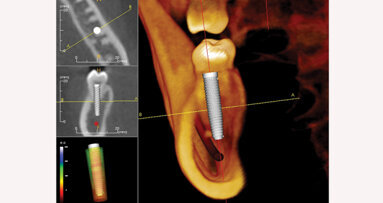

A virtual implant was placed at each site in the software. It was determined that, based on the trajectory of the guide sleeves, that both implant sites were angled to the facial aspect. This would create lingual perforation when the osteotomies were prepared, and a correction would be necessary with the surgical guide that would be fabricated. Additionally, both planned implants would need to be shifted and angled lingually to allow the definitive restoration to have lingual access openings for the abutment screws. Analysis determined that the implant at the central incisor would need to be angled 9° to the lingual aspect and offset to the facial aspect at the crest by 1 mm and the canine angled 15° to the lingual aspect and offset to the facial aspect by 1 mm (Figs. 5a–c).

Figs. 5a–c: CBCT views showing orientation of the diagnostic guide sleeves in relation to the bone present (green line), indicating correction required on both planned sites to have implants placed within the arch. The red line indicates the angle correction, and the yellow line indicates the offset measurement to the facial and lingual aspects. The blue line indicates the newly planned axis of the implant.